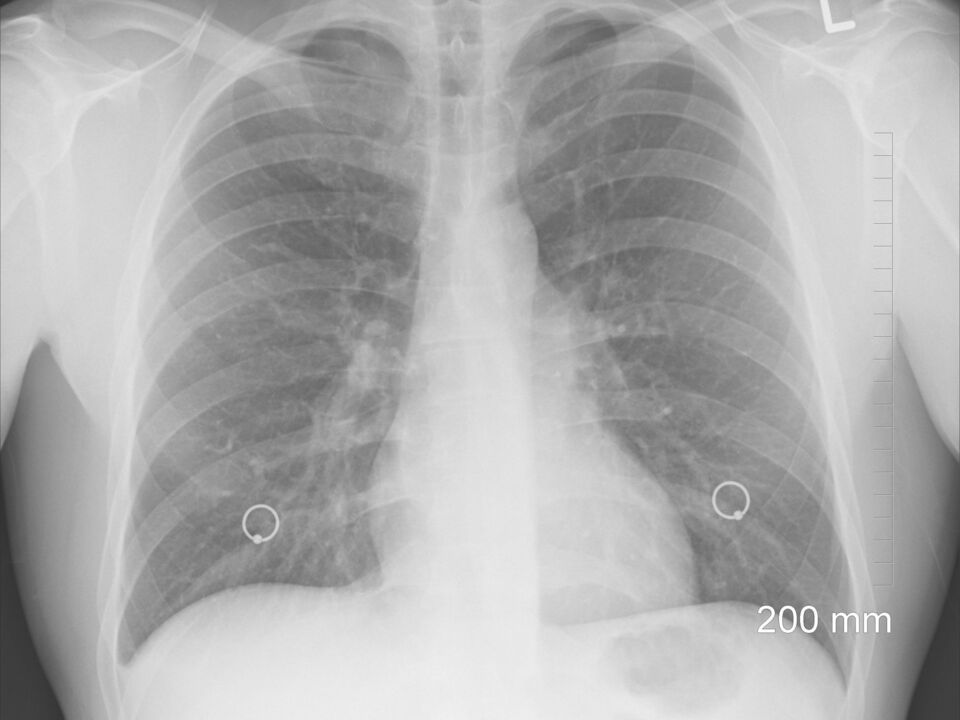

Röntgen

Die Praxis verfügt über eine moderne, digitale Röntgenanlage mit Film-Folien-System. Sofern erforderlich, können wir ohne zusätzliche Wartezeiten die Röntgendiagnostik durchführen.